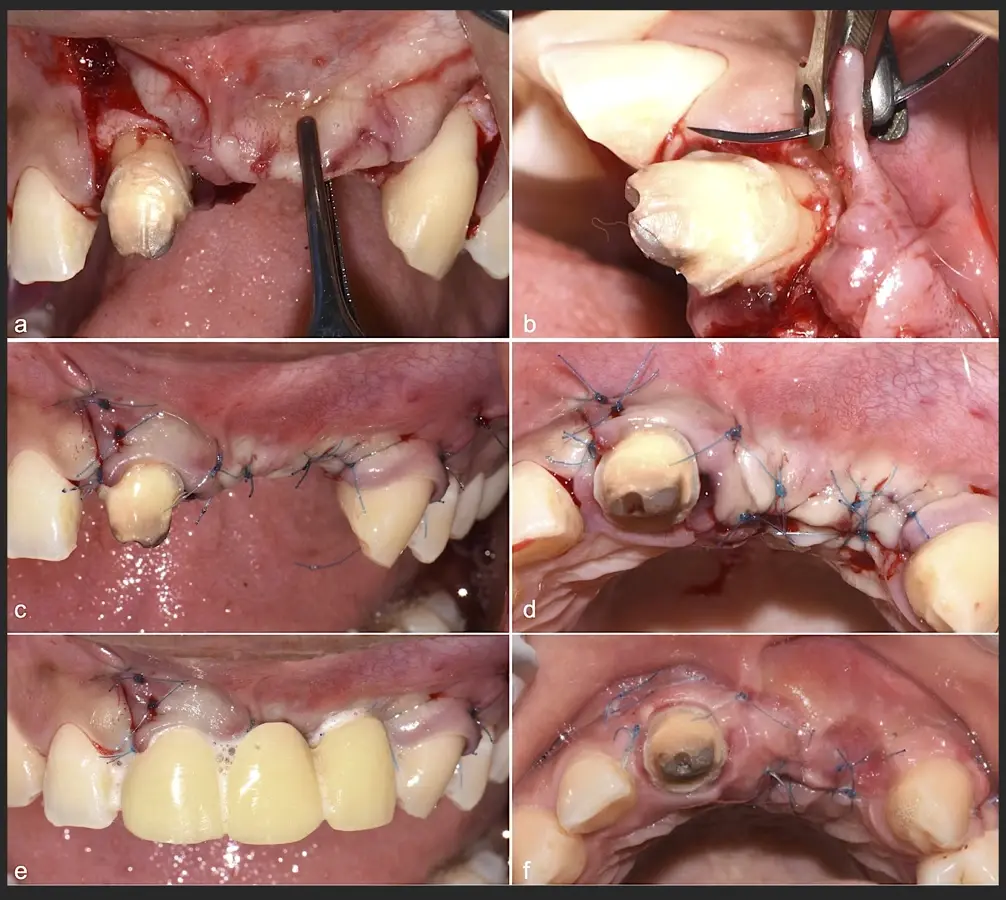

Paciente de sexo femenino de 36 años de edad, llega a la consulta por presentar una restauración protésica inadecuada. En el examen clínico se observa una restauración protésica provisional acrílica sobre las piezas 1.1 y 2.2. Adicionalmente, se aprecia recesión gingival a nivel de la pieza 2.2 y deficiencia horizontal severa de reborde a nivel de la zona edéntula correspondiente a la pieza 2.1. En la evaluación tomográfica se observa ausencia total de tabla ósea vestibular en la pieza 2.2, y se corrobora el déficit en la zona edéntula de la pieza 2.1, para lo cual se indica una reconstrucción de estructuras óseas con hueso en bloque de origen bovino y posteriormente la colocación de implantes dentales.

Figura 35. Decolado a espesor total sobrepasando la línea mucogingival (a, b).

Figura 36. Defecto óseo y severa reabsorción ósea horizontal: vista clínica (a) y corte tomográfico (b).

Figura 37. Liberación del colgajo para asegurar un cierre sin tensiones.

Figura 38. Decorticalización por medio de broca de 1.2 mm de diámetro (a, b).

Figura 39. Uso del inserto plano de punta aserrado para realizar una mayor decorticalización (a). Surcos de vascularización y nutrición (b).

Figura 40. Secuencia de fijación y modelado del bloque óseo con inserto de corte, eliminación de ángulos agudos (a-d).

Figura 41. Modelado del bloque óseo con inserto plano de punta diamantada (a) para redondear los ángulos agudos y así evitar una dehiscencia o fenestración de los tejidos blandos (b).

Figura 42. El proceso de triturado de biomaterial óseo sustituto en bloque (a - d).

Figura 43. Colocación del biomaterial triturado (a - d).

Figura 44. Pasos para la colocación de la membrana de barrera (a - d).

Figura 45. Afrontamiento de colgajo y sutura (a - e). Control a los 7 días postquirúrgico (f).

Figura 46. Control a los 10 días post cirugía.